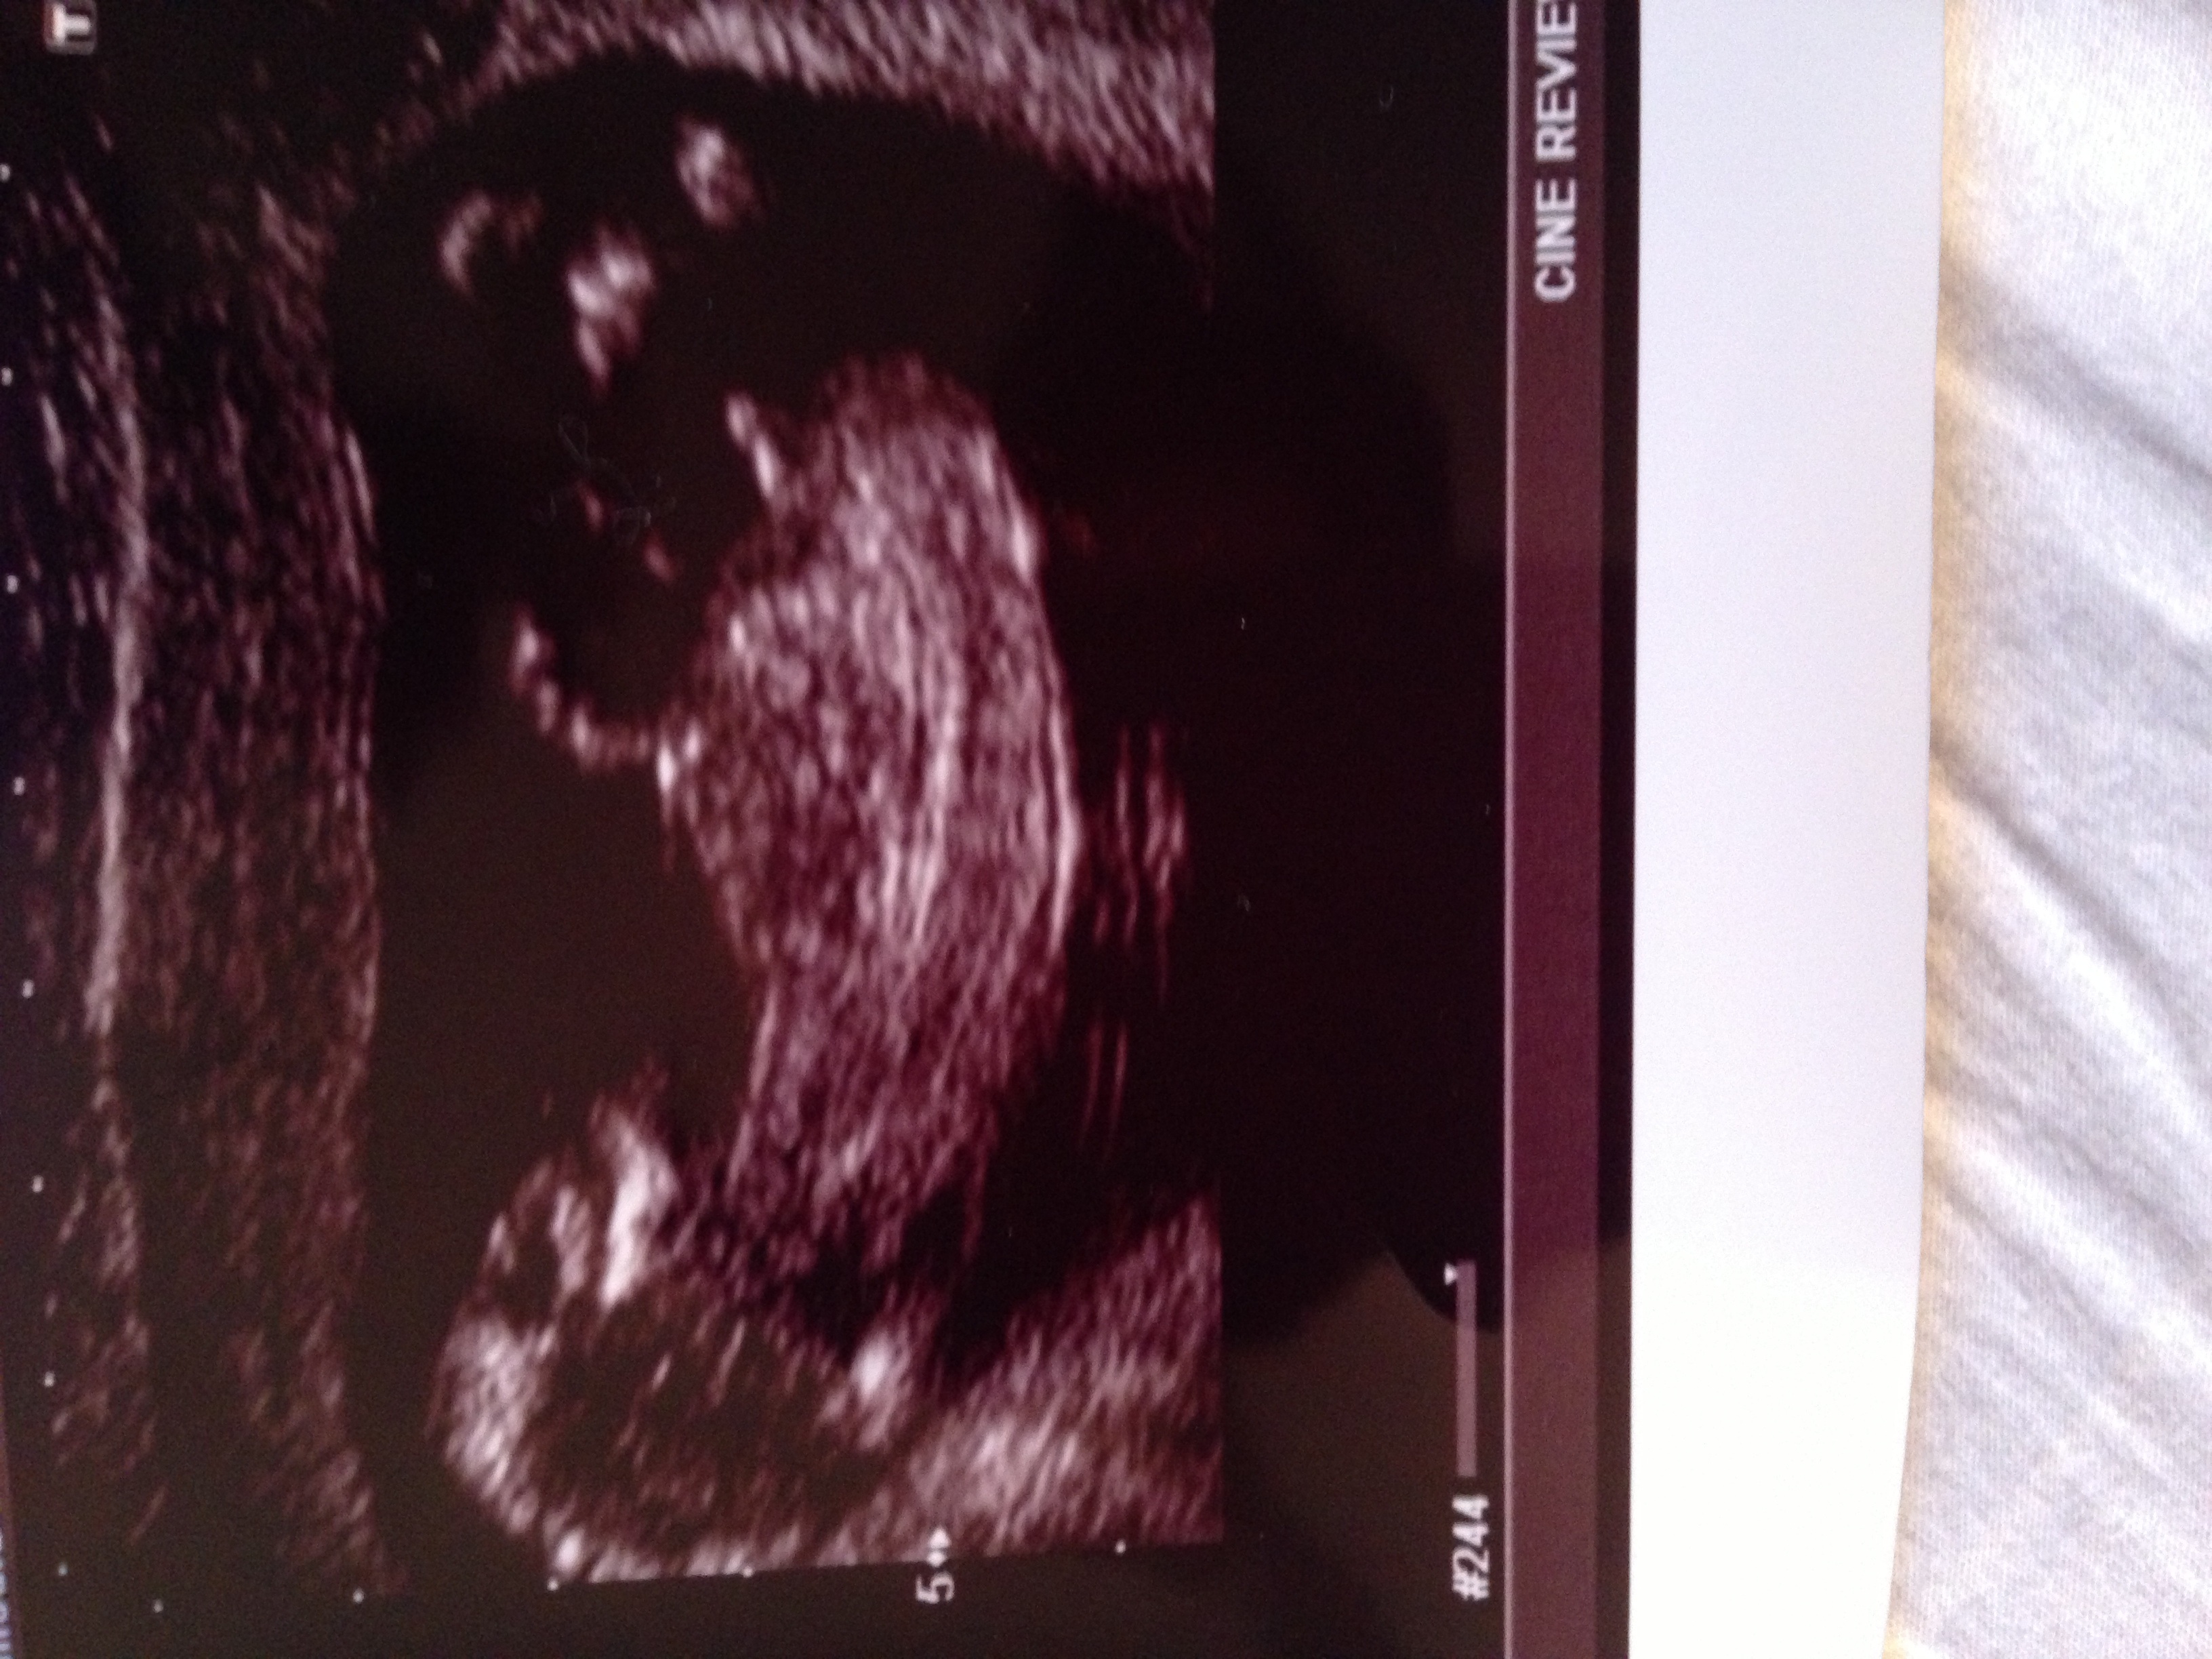

I just had my 12 week ultrasound. Do you think it's too early to tell?

Any help is appreciated! :]

Boy!

Looks like a boy

Definitely a baby boy!!